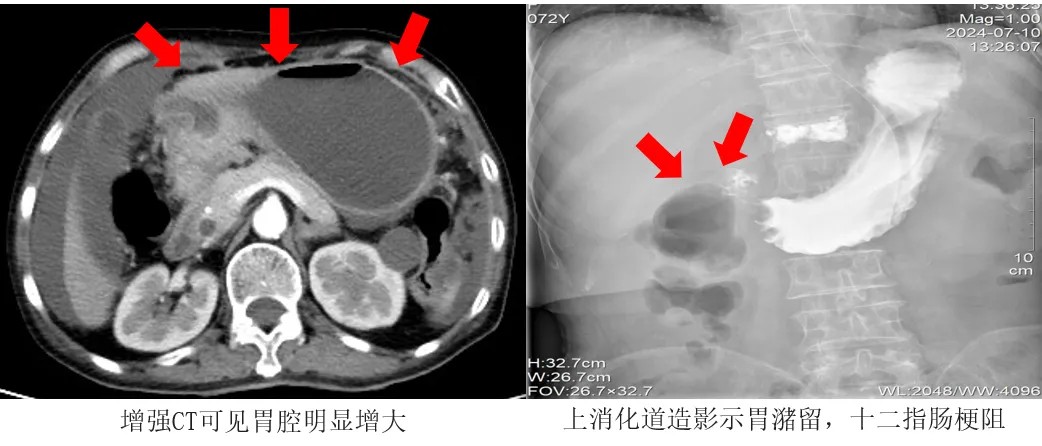

不久前,72歲的王阿姨罹患胃癌,發現時已為癌癥晚期,癌細胞已擴散至腹腔,無法行外科手術根治。但腫大的腫瘤組織嚴重壓迫胃的幽門及十二指腸部分,導致消化道梗阻。

考慮到王阿姨高齡、手術耐受力差,介入科團隊決定為其行十二指腸支架植入術治療,用支架撐開腸道,讓狹窄部位恢復通暢。

術中,醫生拔除胃腸減壓管,隨后通過王阿姨口腔,利用導管與導絲配合,精準進行了幽門插管操作,并成功穿越了狹窄區域。緊接著,他們沿著導絲順利放置了一枚十二指腸支架,且在透視下確認了支架的位置完全符合要求。

術后24小時,王阿姨開始喝水。術后48小時,王阿姨開始進食米湯等流質食物。術后72小時,王阿姨進食蛋羹、爛面條等半流質食物。復查上消化道造影顯示,支架形態、位置均良好,術區未見明顯狹窄及滲漏。王阿姨恢復了正常飲食。